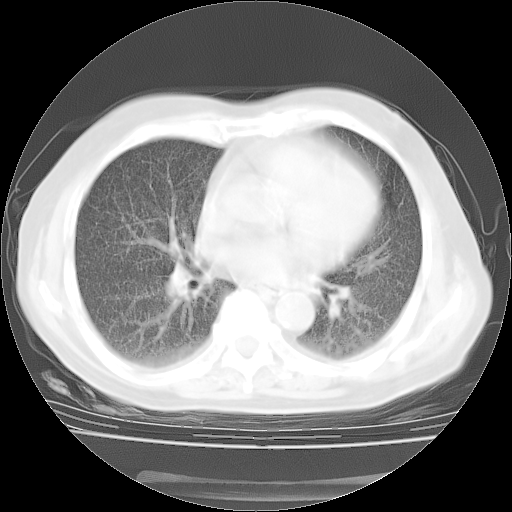

4月14日肺部CT

肺部CT平扫未见异常。